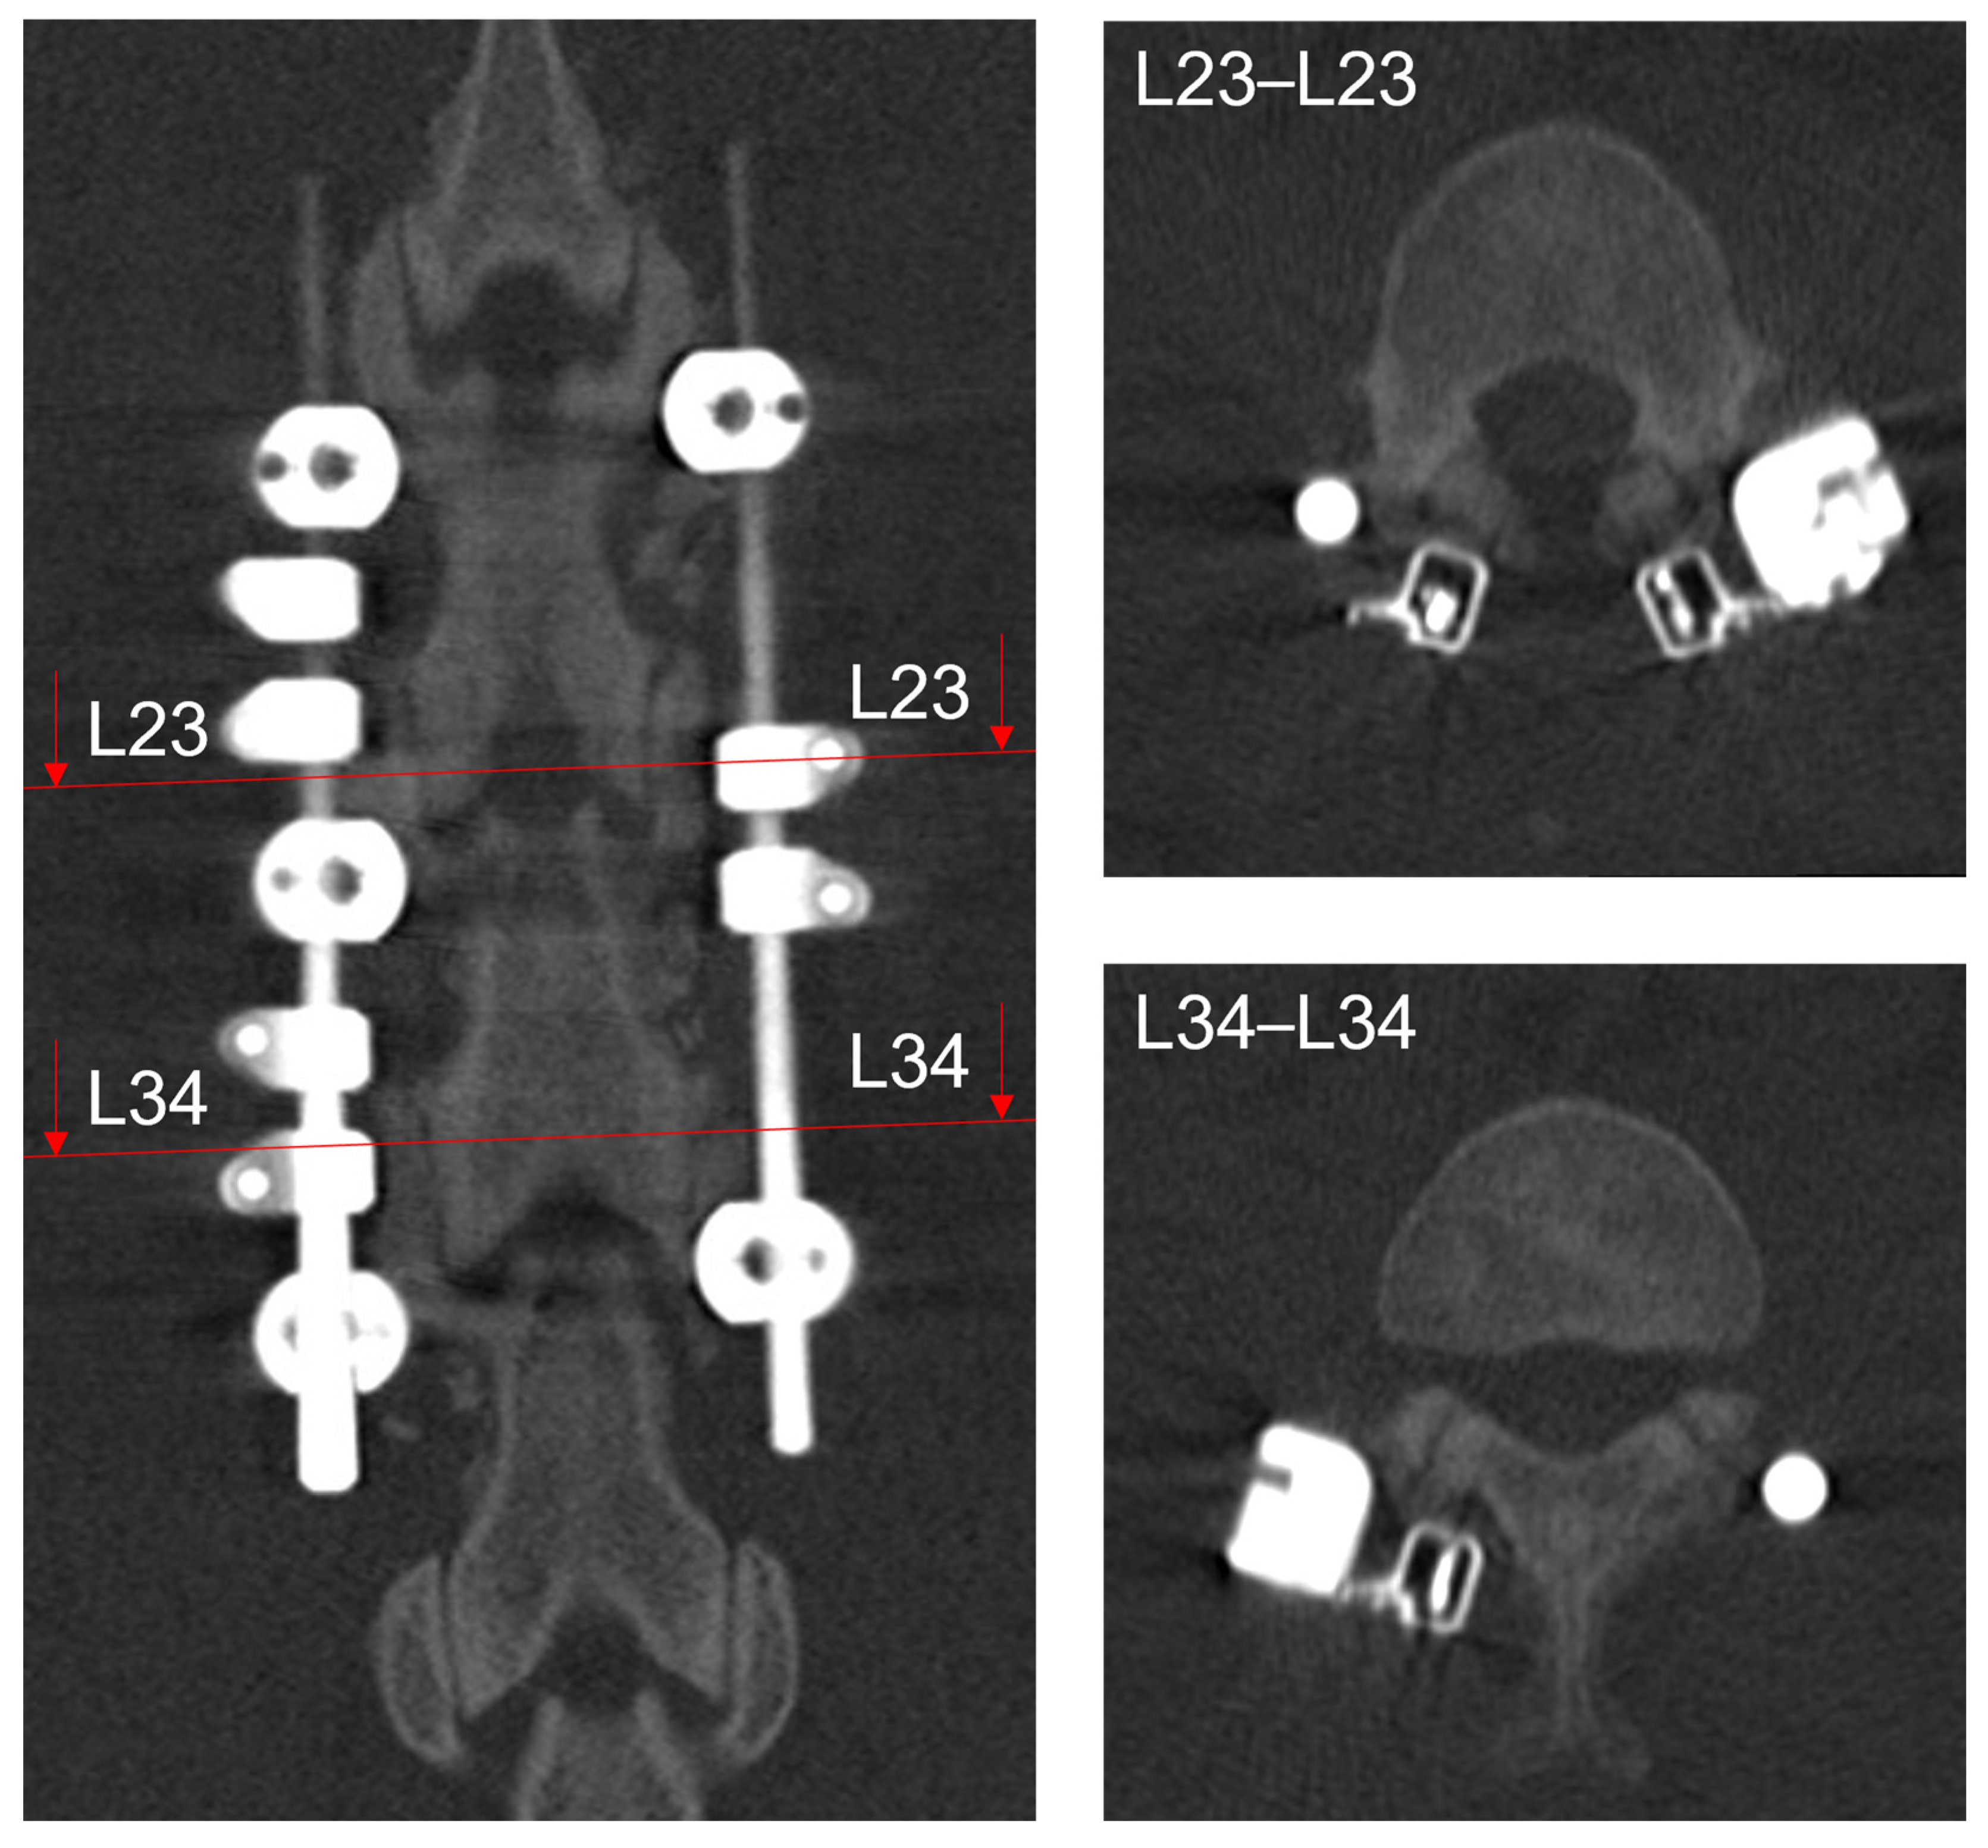

2.2. Animal Study